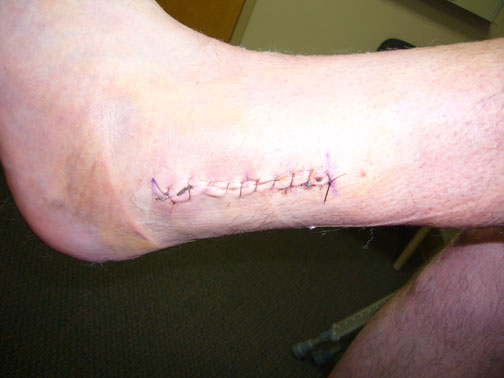

7-30-07 I developed a rash that turned to blisters all around the incision site. It itched horribly at first then turned to pain. The Dr.'s think it was contact dermatitis from the solution they cleaned the suture site with or the Steri strips on 7-17-07.

8-6-07 Starting to heal - only scabs left.